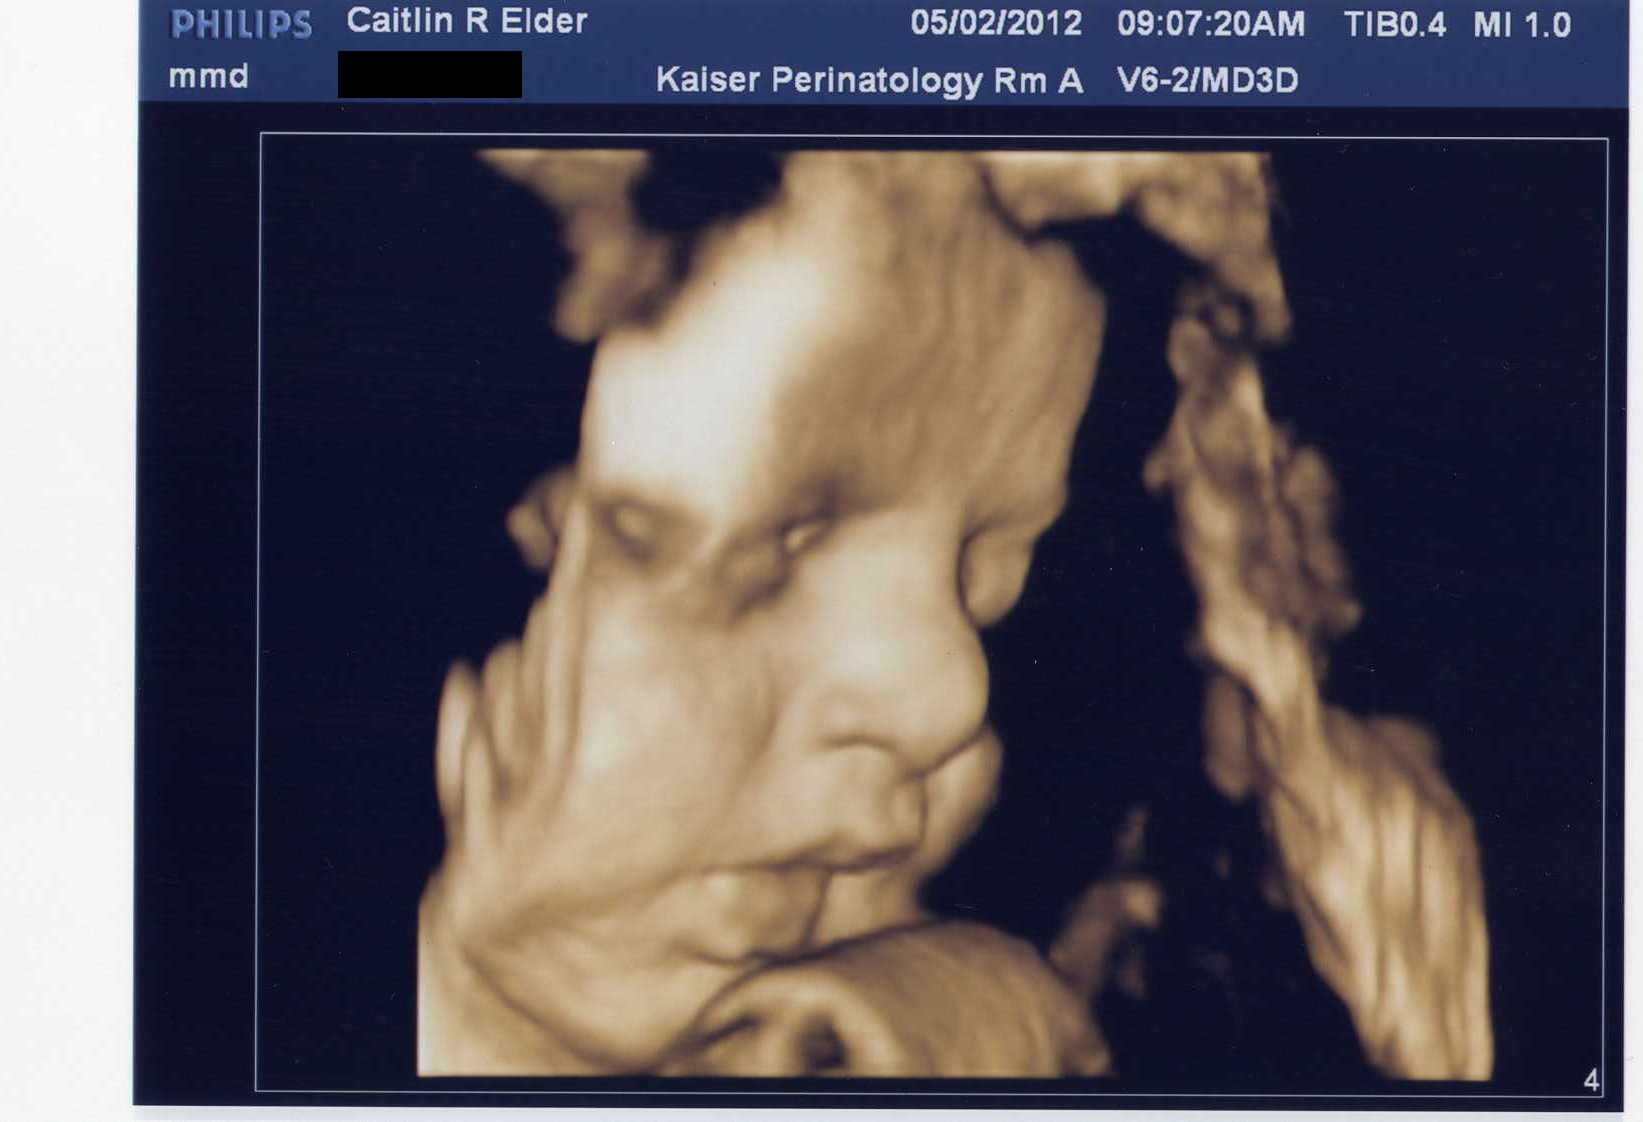

Baby Face

There she is! How beautiful is that face? I just want to kiss those little cheeks.

Isn’t ultrasound technology amazing? It seems a little like cheating to see her face so clearly before she’s on the outside.

I can’t end this post with Mo-bug because it’s supposed to be about #2, so here’s one last (little bit fuzzy) 3-D image of her cute little face. We’ll be able to compare these pictures to the real thing in T-minus 8-ish weeks. Oh man, all of a sudden that doesn’t seem like a very long time. I better go clean something…or eat some ice cream. Hmm…She does have quite a bit of weight to put on…I definitely choose ice cream.